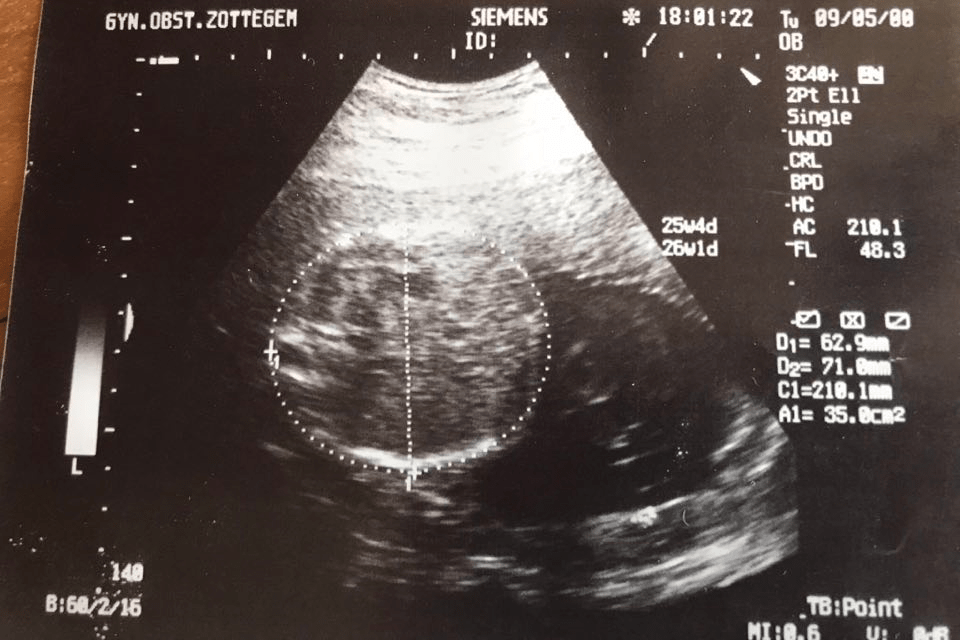

Prenatale screening en diagnostiek

Prenatale screening

Prenatale diagnostiek